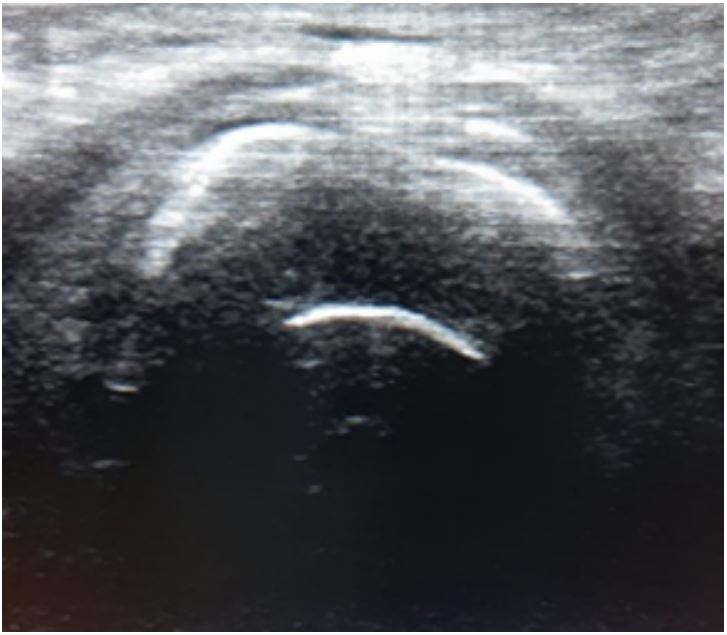

También se puede confirmar el adecuado posicionamiento del tubo orotraqueal de forma más rápida, y a la cabecera del paciente, mediante el uso de ecografía (figura 1), visualizando el artefacto en cola de cometa para las intubaciones traqueales, y en el caso de intubaciones esofágicas, el signo del doble tracto (55), con especificidad del 100 % y sensibilidad del 98,3 % (56,57).